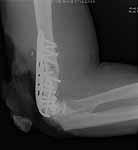

He was treated with IV antibiotics and no sign of infection was seen. After antibiotics were stopped, he still showed no sign of infection. He was offered a total elbow replacement which he refused since he has a handicapped child that he needs to care for, and he did not want to accept the lifting restrictions. He was offered an elbow fusion which he refused because he did not want the stiffness, but he did agree to fixation across the elbow without taking out the joint, even knowing that he would still have stiffness and even with later soft tissue release might not be any different than a fusion. The second revision including cross elbow fixation is in files (2nd revision).

2nd revision

This surgery was done 9/27/04. He was grafted with DBX and BMP, and debrided to bleeding bone with good contact, and compressed with a lag screw. At surgery there was no sign of infection. 3 sets of deep bone cultures came back "no growth" and a bone biopsy did not reveal any inflammatory cells. Sed rate was 21 and C-reactive protein 0.4.

He continues without sign of infection. But his sed rate is 65 and C-reactive protein 21. Despite cast immobilization, his current x-rays (11/17/04) show another failure of fixation (files current)... He still does not want replacement.

current